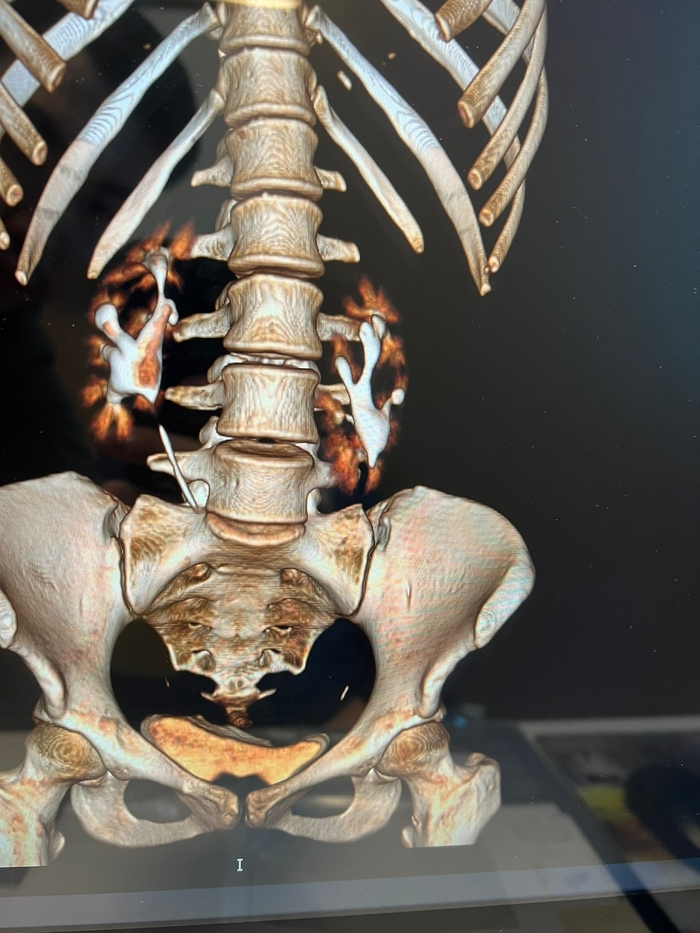

Такое состояние привело меня в Саратов, в педиатрическое отделение УКБ Миротворцева. На основании уросцинтиграфии и компьютерной томографии с контрастом был поставлен истинный диагноз: "Пояснично-подвздошная дистопия обеих почек, ротация левой почки. Гипоплазия левой почки. Вторичный пиелонефрит с потерей функции почек". С 3 до 10 лет функция почек стремительно падала, исследование 2010 года:

КТ контроль через пол года после операции: